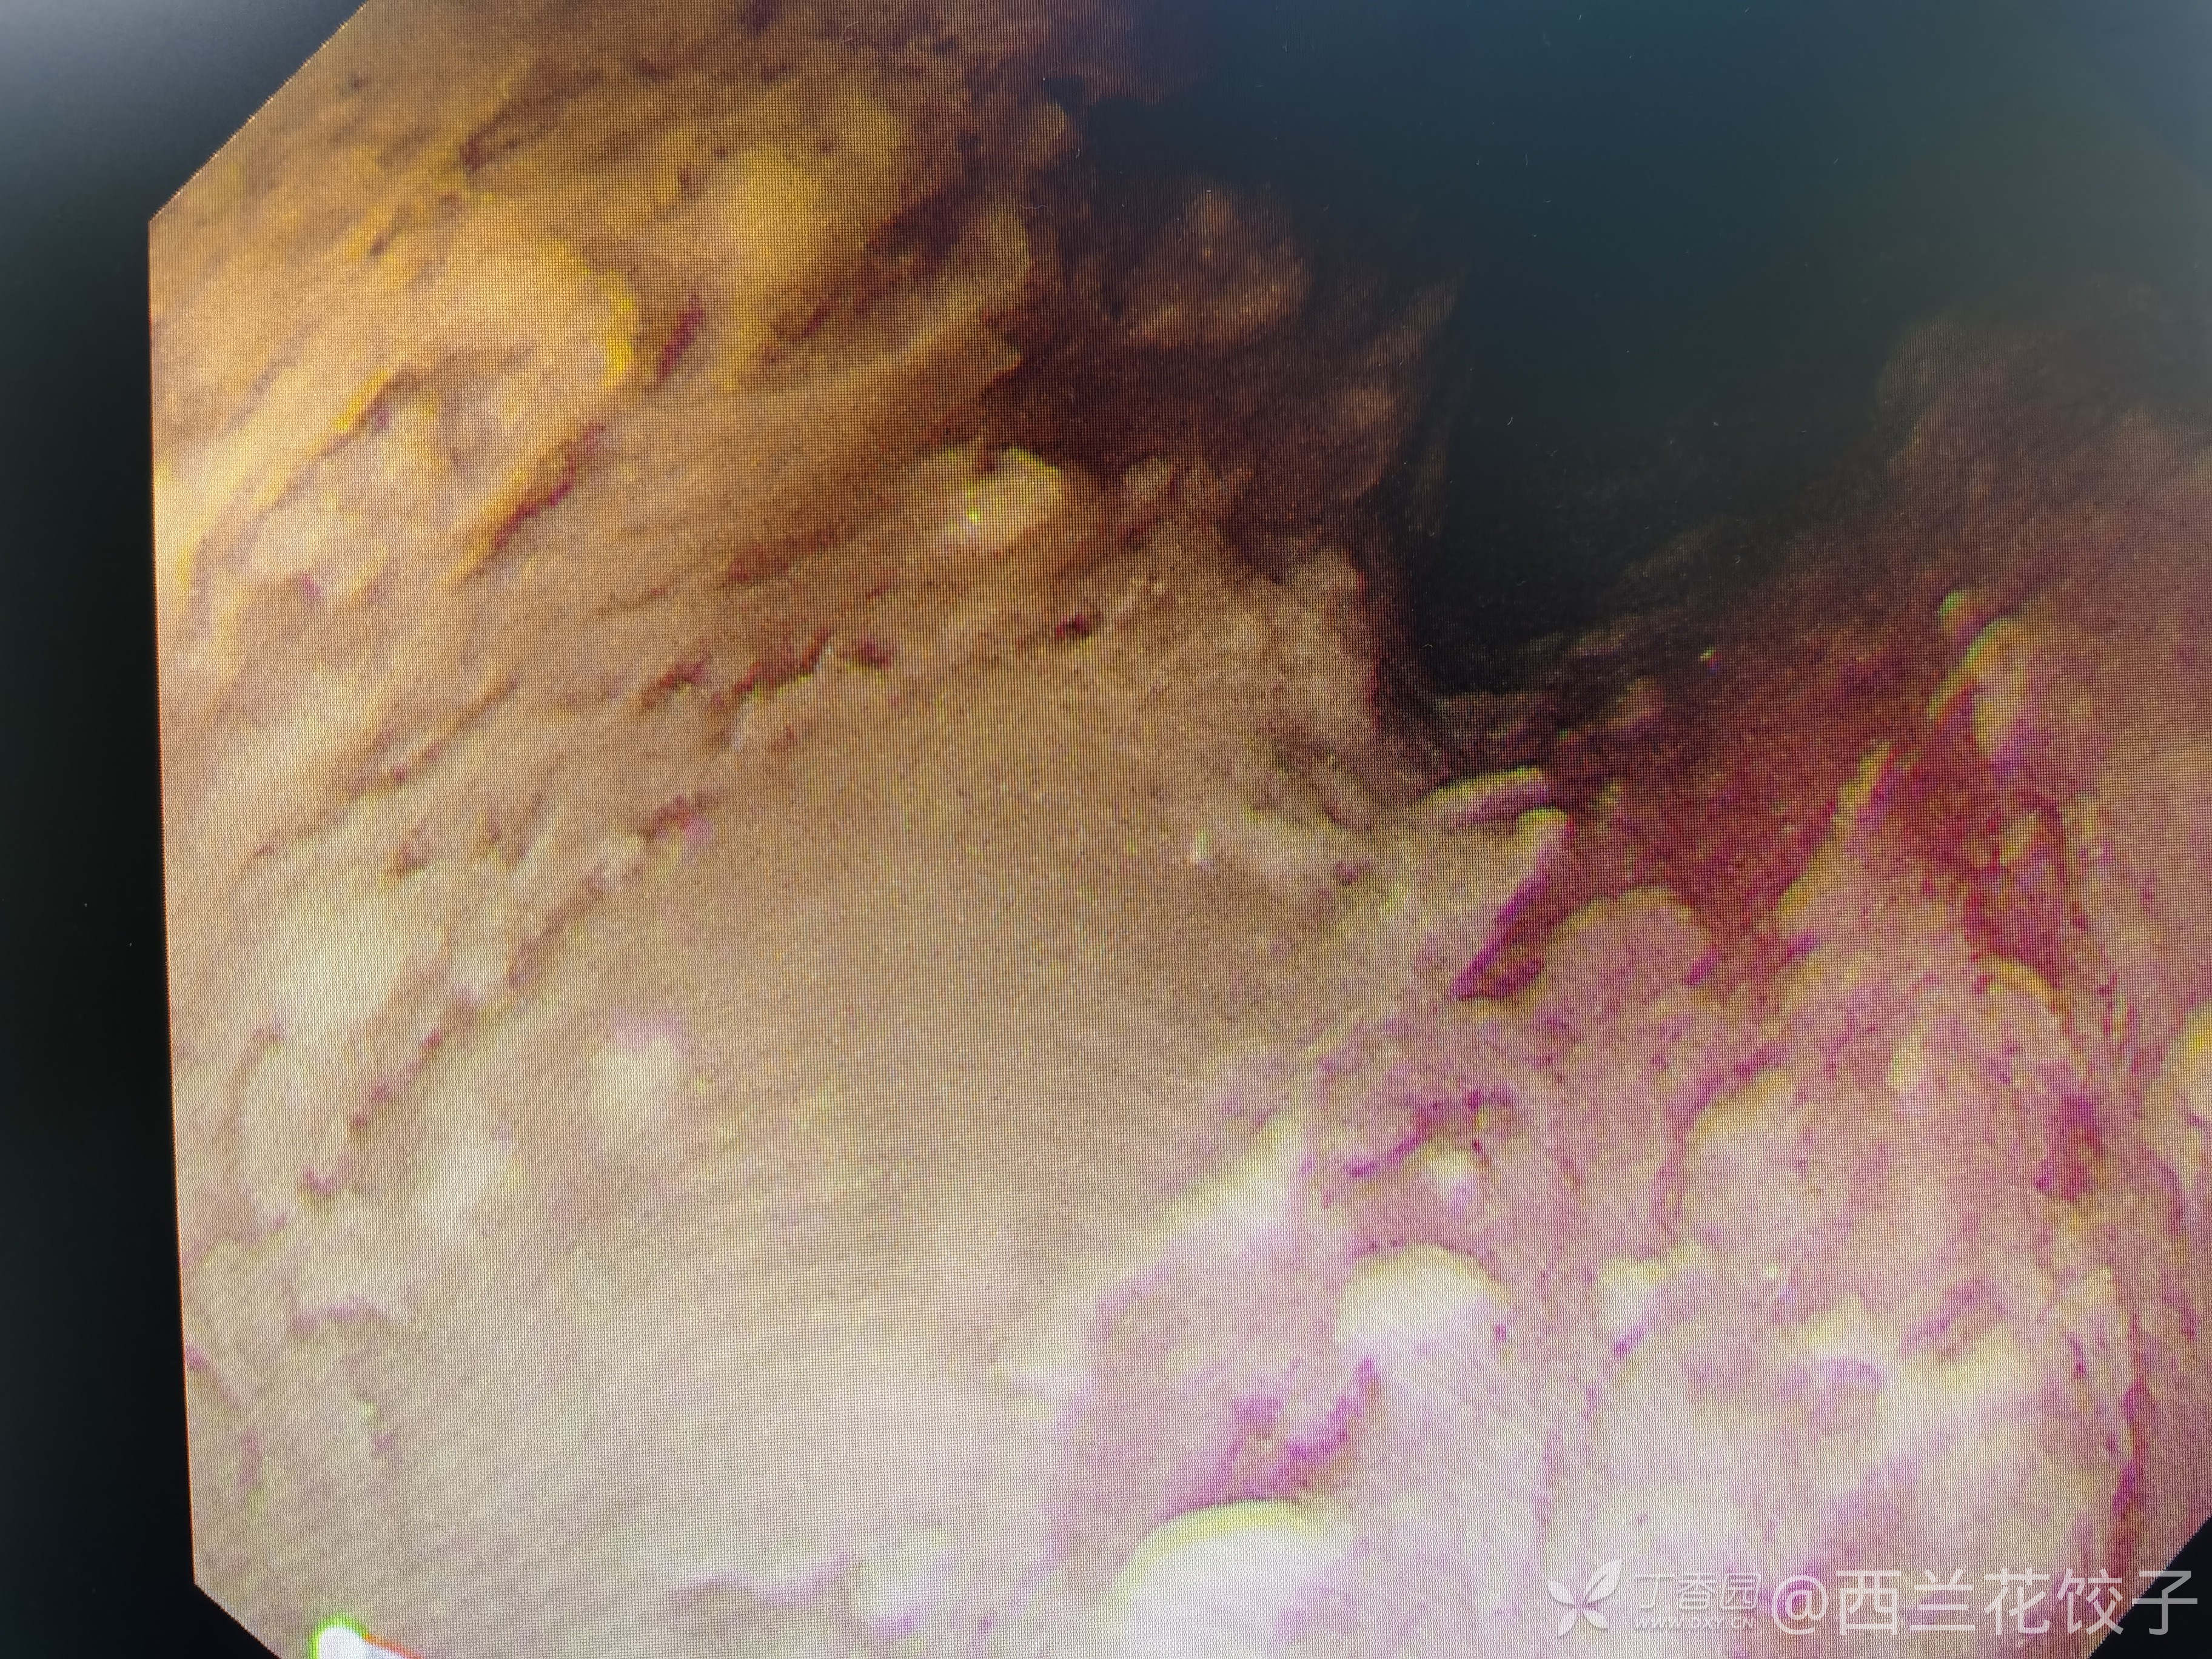

辅助检查:胃镜检查如下,食管内可见大量食物残渣及液体,胃腔内未见明显异常,胸腹部Ct如下,新冠核酸阴性。